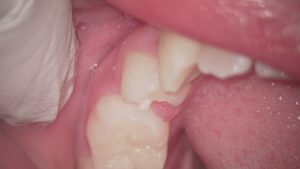

歯の形態異常である中心結節という突起は、小学生くらいの永久歯が生えてきた時期、ご家族の仕上げ磨き時に気づくこともあります。

下の奥歯と前歯の間くらいの小臼歯という歯に生じやすいです。

6歳臼歯の手前の小臼歯生じやすい